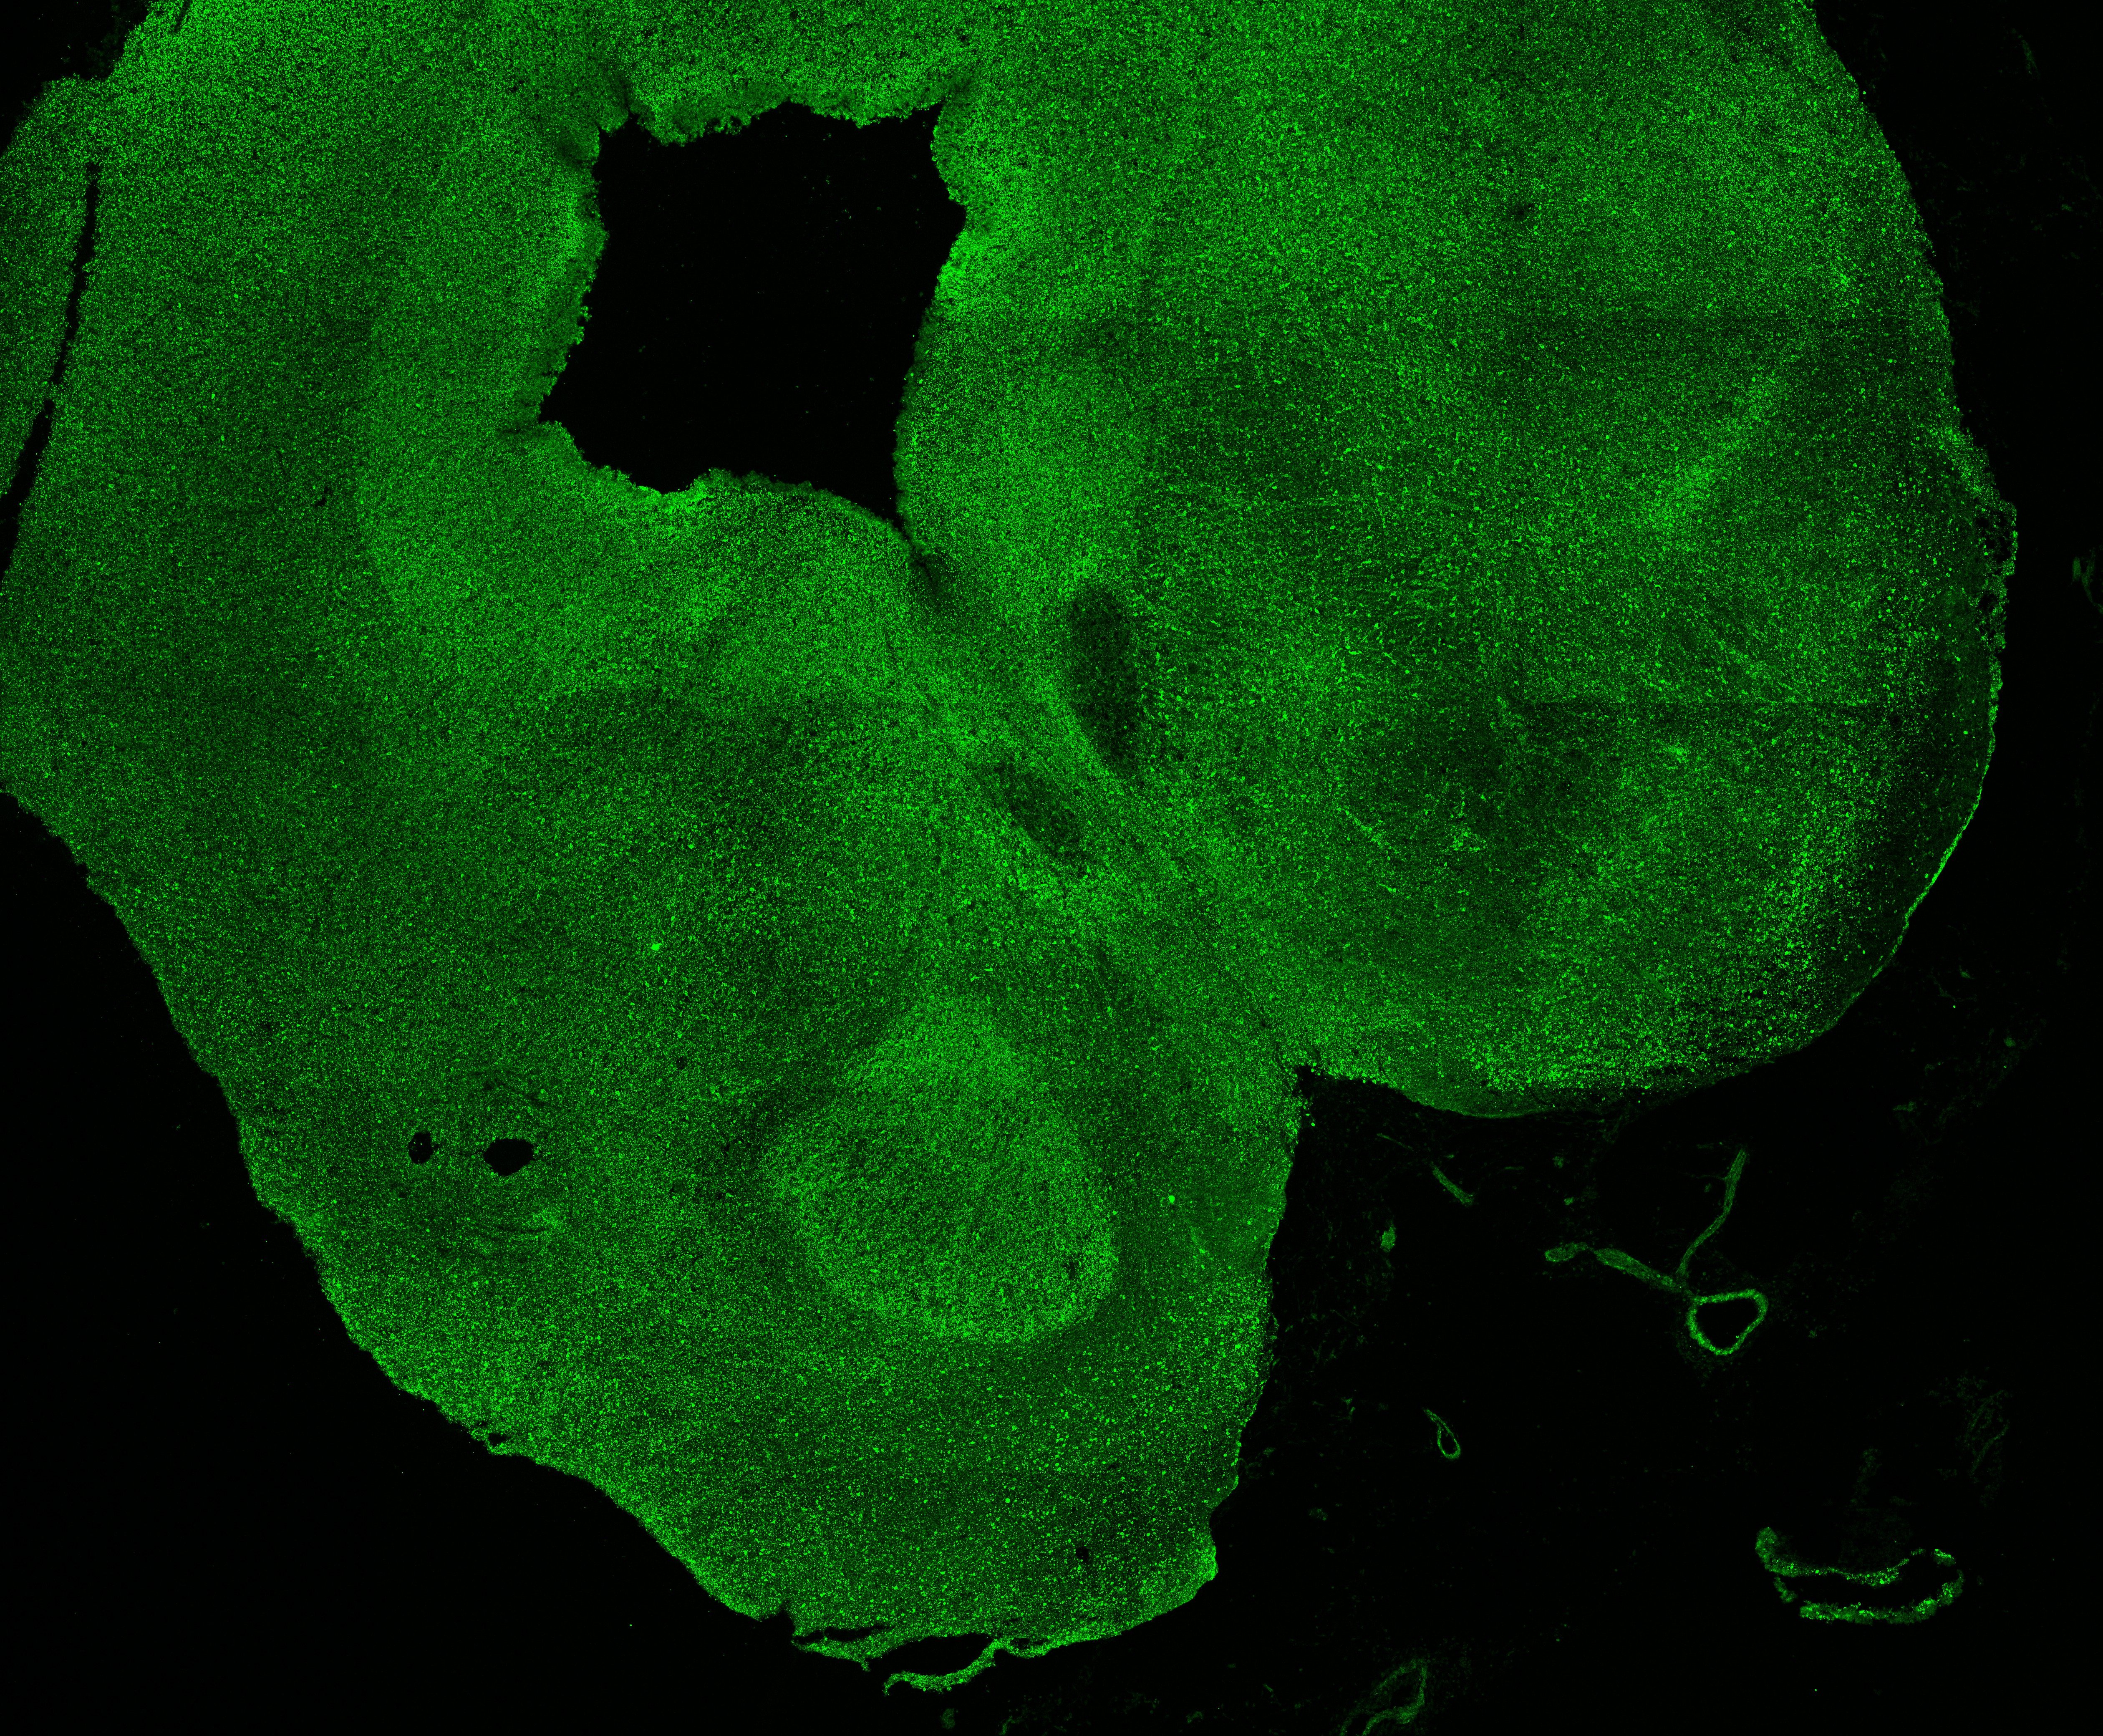

An in vivo and in vitro spatiotemporal profile of human midbrain development

An anatomical analysis of the developing human midbrain from 6 post-conceptional weeks (PCW) to 22 PCW reveals increased tissue complexity, characterized by the emergence of dopaminergic nuclei, as highlighted by immunofluorescence analysis for tyrosine hydroxylase (TH).

11PCW

DAPI

11PCW human midbrain

MAP2

SOX2

Merged